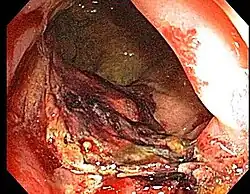

- Etiology: obliterative endarteritis and chronic mucosal ischemia, leading to progressive epithelial atrophy and fibrosis. Ultimately, development of a chronically ischemic intestine prone to fibrosis and bleeding

- Symptoms: diarrhea, obstructed defecation (if strictures), bleeding, rectal pain, rectal urgency, and fecal incontinence. Rarely fistulas, SBO

- Endoscopy (Argon plasma coagulation) - benefit for bleeding